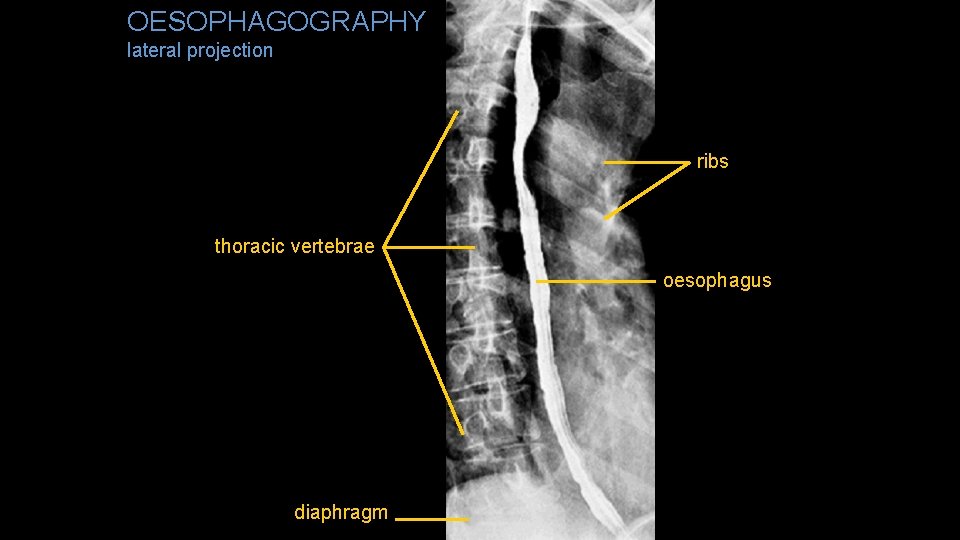

OESOPHAGOGRAPHY lateral projection ribs thoracic vertebrae oesophagus diaphragm